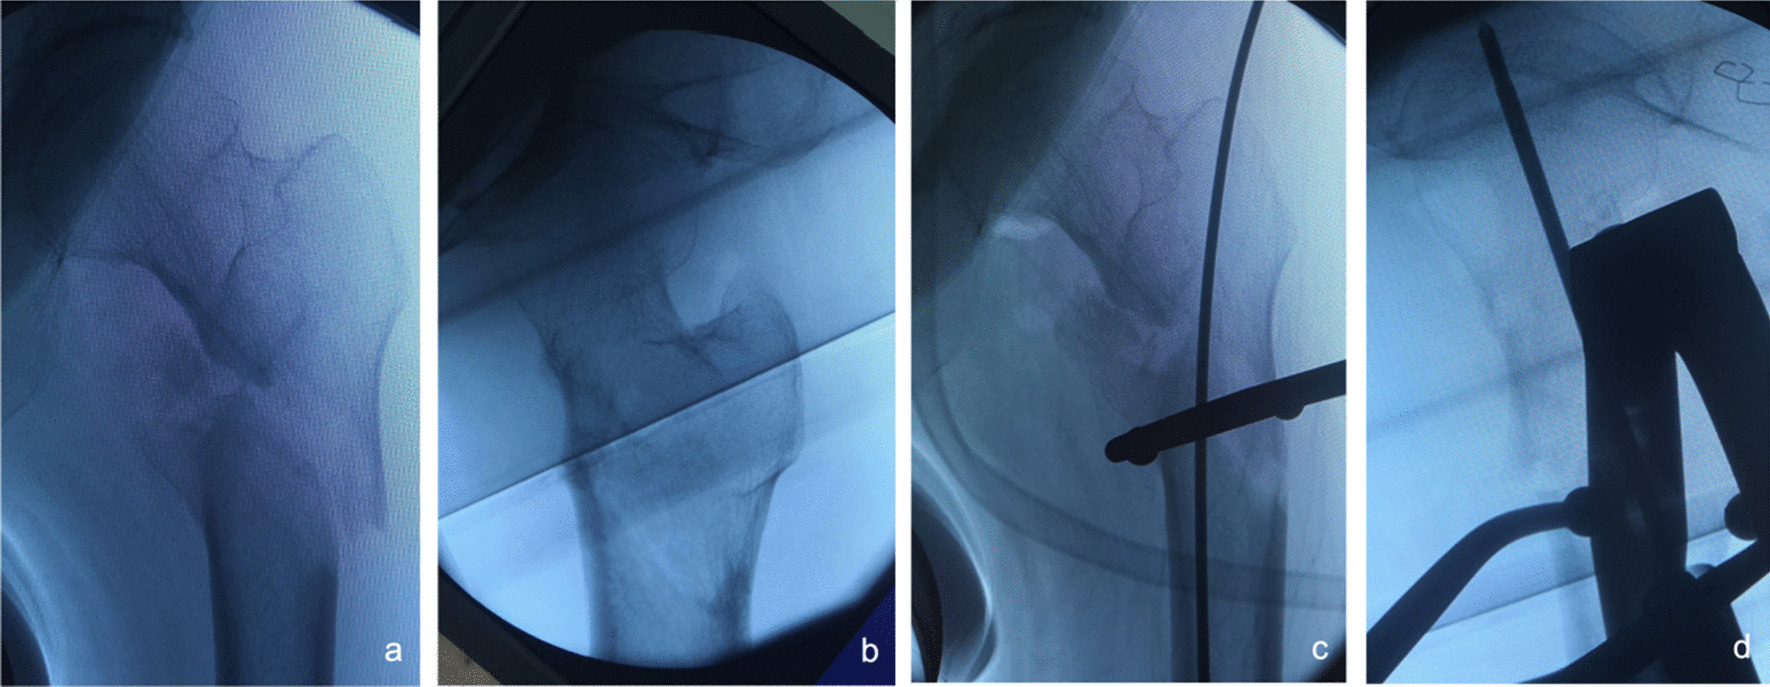

Fig. 3.

Anteroposterior and lateral X-ray films before and after reduction in patients with difficulty in reduction on the sagittal plane and pronation displacement of the proximal fracture segment a, b Before reduction; c, d After reduction (one head placed in front of the proximal fracture segment and the other head behind the greater trochanter)